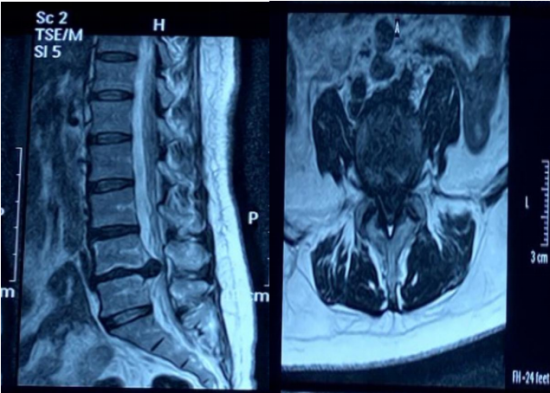

52岁患者王女士,近3个月腰痛难忍且伴左下肢放射痛,近期因劳累加重、行走困难、保守治疗无效来到龙中医一院骨伤三科就诊。腰椎MRI显示,患者L4-5椎间盘向左突出,压迫硬膜囊及左侧神经根。

患者术前影像资料